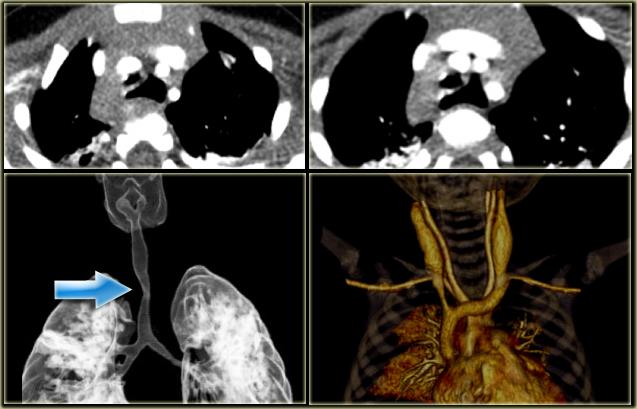

Azygos Continuation of IVC

- Abcense of hepatic segment of IVC with azygos continuation.

- IVC interrupted above level of renal veins.

- Association with congenital heart disease and polysplenia.